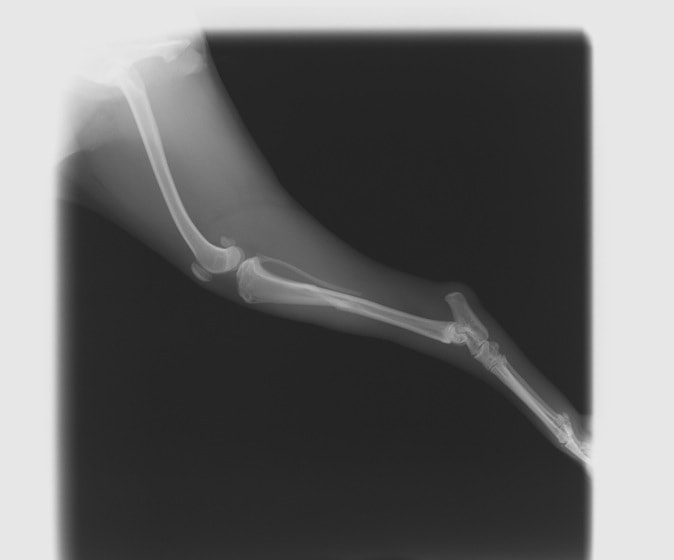

ペルシャ猫 11ヶ月齢 雄

他院にて左大腿骨遠位の成長板骨折(salter-harrisⅠ型)が認められており、治療相談を目的として来院。当院にて、キルシュナーワイヤーを用いたピンニングにより骨折部位の整復を行いました。術後の経過は良好で、現在も経過観察中です。

術前レントゲン